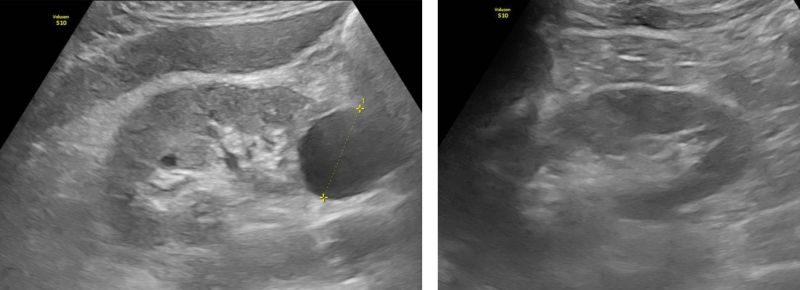

Hình ảnh nốt vôi hóa gan phải, nang thận phải

Siêu âm ổ bụng phát hiện nốt vôi hóa gan phải và nang thận phải. Trên phim chụp CT có tiêm thuốc cản quang, ghi nhận hình ảnh gợi ý viêm thận – bể thận phải, kèm nang thận phải.